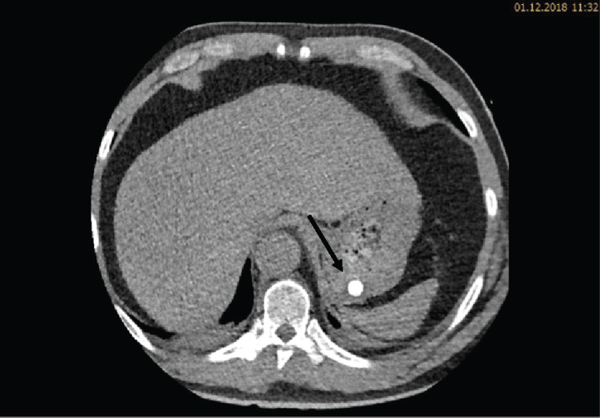

During the ICU stay, the patient’s condition was stable. Bed rest was prescribed, and strict blood pressure control was performed with continuous intravenous infusion of labetalol and urapidil targeting a systolic blood pressure below 120 mmHg. Oral antihypertensive treatment with nebivolol, moxonidine, and amlodipine was started. Continuous labetalol and urapidil infusions were stopped on day three. Due to hypokalemia, potassium chloride tablets were prescribed. Five days after admission, another CT angiography was performed to review the development of the hematoma. The CT scan revealed a reduction of the hematoma. Furthermore, in the arterial phase, a faint hyperdense lesion (max. 348 HU (Hounsfield units), ) was detected in the posterior fundus of the stomach (Figures 1(a)–1(c)). The previously acquired native scan was performed only for the thorax and did not include the stomach; therefore, it was not possible to determine with certainty whether the lesion reflected contrast media extravasation or foreign material. However, due to the intramural hematoma of the descending aorta, the possibility of an aorto-gastric fistula was considered. Additional measurements of hemoglobin were performed to screen for relevant bleeding. As the patient’s hemodynamics as well as hemoglobin levels remained stable, no further investigations (e.g., gastroscopy) were undertaken and our strategy remained expectative. At the same time, we were searching for an alternative clarification of the findings. We found that (1) the patient had ingested two potassium chloride tablets five hours before the CT scan, (2) potassium chloride tablets have radiopaque properties [1, 2], and (3) there were other hyperdense but sharply demarcated structures in the stomach and in the small bowel (density max. 1724 HU) (Figures 2, 3(a), and 3(b)). After putting all available information together, we suggested that the radiopaque lesion in the stomach was caused by the remnants of a degrading potassium chloride tablet ingested by the patient hours before the CT investigation whereas the other potassium chloride tablet ingested at the same time had been propulsed to the small bowel without being degraded in the stomach.

(a)

(b)

(c)